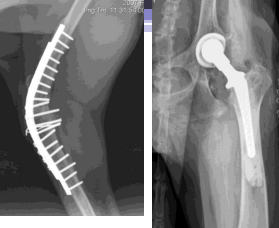

Triple Pelvic Osteotomy

Physically rotating acetabulum

Sig: Age <12m, laxity but no OA, Lg breeds, angle of reduction ≤30°

Use: Preventative and palliative, rotate acetabulum to increase coverage, cut ilial body, pubis, ischium

Cut in 3 places, place plates to stabilize

Pro: 90% success rate

Con: OA may still progress but slower

Total Hip Arthroplasty

Use: Salvage, replace end-stage joint with prosthesis

Pro: Near-normal fxn, Quick

Cons: expensive